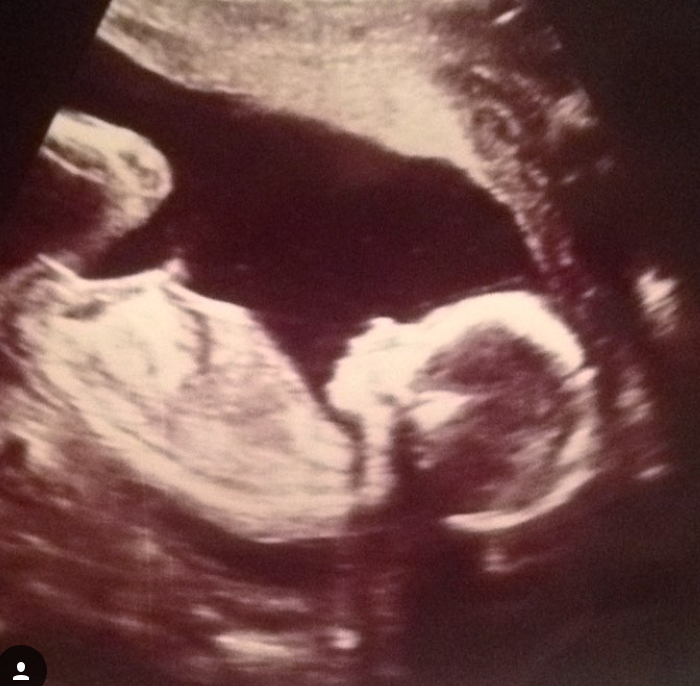

18 haftalık bebek ne kadar olur. Online olarak hazırlanmış hesaplama cetvelleri üzerinden 18 haftalık gebelik kaç aylık olur sorusunun cevabı kolay ve hızlı bir şekilde öğrenilebilir. Ayrıca bebeğinin tekmelerini ve yumruklarını hissetmeye. Bebek hareketlerinin azalması anne tarafından bebeğin hareket etme alışkanlıklarının değişmesidir. 18 haftalık bebek gelişimi18 haftalık bebek boyu12 5 14 cm18 haftalık bebek kilosu150 170 gr 16 haftalık bebeğinin dönmeleri tekmeleri ve yumrukları senin bile hissedebileceğin kadar şiddetlenmeye ba.

18 haftalık gebelikte bebek ağırlığı 150 gram civarında baş bölgesinden kalçalarına kadar olan uzunluğu ise ortalama 12 5 ila 14 cm aralığında oluyor. 18 haftalık gebelikte anne karnı ne kadar büyür. Her bebek baştan itibaren kendine özgü bir hareket etme alışkanlığı geliştirir.